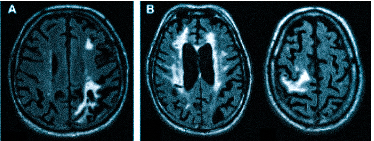

Множественные ишемические очаги при сосудистой деменции на МРТ: отсутствие памяти на недавние события и неадекватное поведение не являются признаками старости, своевременная диагностика деменции и патогенетическая терапия помогут замедлить прогрессирование болезни

демиелинизацию при рассеянном склерозе и иных атрофических процессах;

острые (ишемический или геморрагический инсульт) и хронические нарушения мозгового кровообращения.

Что покажет МРТ головы с контрастом